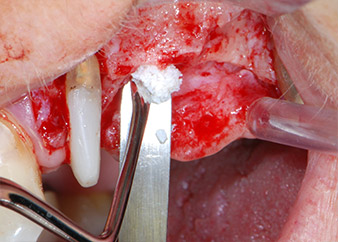

Prior to implant placement, and following verification of an intact Schneiderian membrane (Fig. 9), the internal sinus floor was augmented at both implant sites by means of xenogeneic bone substitute material (Bio-Oss, Geistlich Biomaterials) (Fig. 10).

Fig. 10: Introduction of xenogeneic bone substitute material into the implant osteotomy for internal sinus augmentation. The material was carefully condensed in an apical direction with the ball-ended CPITN probe (not shown).

Bone deficiencies around the implants, at the mesial aspect of tooth 27 and around the buccal root of tooth 24, were filled with xenogeneic bone substitute particles and covered with an absorbable collagen membrane (Bio-Gide, Geistlich Biomaterials) for GBR augmentation (Figs. 13 and 14).

Xenogeneic bone substitute material

Fig. 13: Xenogeneic bone substitute material was used to fill the remaining osseous defects …